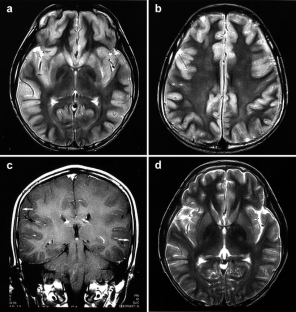

We document the MRI features in six patients aged 5–14 years with acute encephalitis following measles. The diagnosis was made on a characteristic morbiliform rash and detection of specific IgM and IgG antibodies. The symptoms of encephalitis occurred 1–11 days after the appearance of the rash. All patients underwent MRI within 1–4 days of the onset of neurological symptoms. Diffusion weighted images (DWI) were obtained in three patients. In all patients, T2-weighted images showed widely distributed, multifocal high signal in both cerebral hemispheres with swelling of the cortex, with bilateral, symmetrical involvement of the putamen and caudate nucleus. The lesions had showed low apparent diffusion coefficients. Three patients showed subacute gyriform haemorrhage, and asymmetrical gyriform contrast enhancement on follow-up MRI.

Fig. 3a-d.